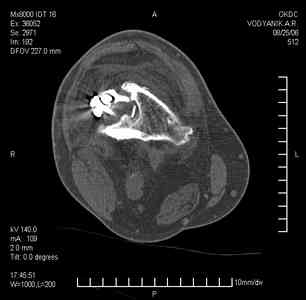

Уважаемые коллеги,В ортопедическое отделение обратился пациент: мужчина 47 лет, который в течение 4-х лет дваждыполучил травму костей, образующих правый коленный сустав. В 2002 v внутрисуставной оскольчатыйперелом проксимального метаэпифиза правой большеберцовой кости; в 2005 v внутрисуставнойоскольчатый перелом дистального метаэпифиза правой бедренной кости. В обоих случаях в разных лечебных учреждениях проводилось оперативное лечение переломов.При осмотре в отделении на основании результатов клинического осмотра и данных визуальныхметодов обследования поставлен диагноз:тугой ложный сустав дистальной трети правой бедренной кости, состояние после накостногоостеосинтеза перелома типа 33-В2.2 ; несросшийся перелом надколенника; неправильно сросшийсяперелом латерального мыщелка правой большеберцовой кости, состояние после металлоостеосинтезаперелома 41-В2.2; сочетанная осевая деформация правой ноги: варусная деформация правого бедра,вальгусная деформация правой голени; посттравматический артроз коленного сустава 4 ст по Kellgren-Lowrence; выраженное нарушение функции ходьбы и опоры. Внешний вид ноги больного, данные рентгенографического обследования и избирательно выделенные компьютерные томограммы приведены в приложении. В именах КТ использовано кодирование уровня по АО, т.е. _41, например, означает проксимальную треть голени.В отделении намечен v очень предварительно v следующий план лечения: 1. Иметь ввиду перспективу тотального эндопротезирования коленного сустава. 2. С учетом п.1 при проведении действий, направленных на устранение ложного сустава бедренной кости не использовать материалы, не подвергающиеся трансформации. 3. В ходе операции, направленной на устранение ложного сустава: А. удалить все металлоконструкции; Б. ревизовать зону пролежня под пластиной на бедре, при наличии признаков достаточной жизнеспособности кости выполнить остеопериостальную декортикацию, дрилинг ложа пластины; В. Удалить рубцовую ткань по плоскости ложного сустава, и в пространстве между костными форагментами, насечь обращенные друг к другу поверхности. Ввести штифт с блокированием (например Stryker с учетом особенностей расположения дистальных блокирующих винтов у этойконструкции). Осуществить остеосинтез с учтанением варусной деформации бедренной кости. Пространство в зоне ложного сустава и пустоты в метафизе бедренной кости заполнить резорбирующимся цементом на основе гидроксиапатита кальция. Для дистальной фиксации использовать винты с переменным шагом резьбы. Вариант:, винты вводить после заполнения метафиза цементом. Дополнительные виды создания межфрагментарной компрессии во встречно-боковом направлении обсуждаются. Г. Быть готовым к кровопотере. Д. Учесть высокий риск инфекции, тромбоэмболических осложнений. Е. Вопрос о внешней иммобилизации решить по результатам оценки стабильности остеосинтеза. Вариант - одноосевой стержневой аппарат для шунтирования гвоздя с модулем на голени и дистракцией коленного сустава в течение 3-5 недель. Просим вашей критики намеченного плана и конструктивных предложений. С уважением к сообществу, Ординатор В.С. Саплин

Движения приличные, есть за что бороться. Такая ротация голени кнаружи, если она действительно есть (для уточнения можно сделать КТ на уровне обоих метафизов и бедреных, и берцовых ксотей, не меняя положение ног во время съемки), большого значения не имеет. А уж на фоне всего остального тут - вообще говорить не о чем.